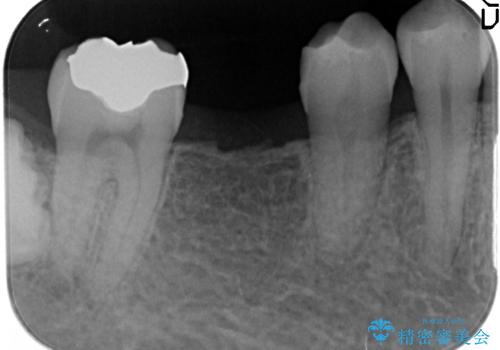

- 右下の奥歯にインプラントを入れたいと来院。

抜歯から時間が経っており、骨が十分あったためすぐにインプラントを入れることが可能でした。骨も補う必要がありませんでした。

インプラントの術式は比較的単純で、難しくないですが、予後を見据えて角化歯肉を増やす手間をかけることが大変重要です。

長期的な予後を見据えた治療をしてもらえる病院を、慎重に選んでいただくことをお勧めします。